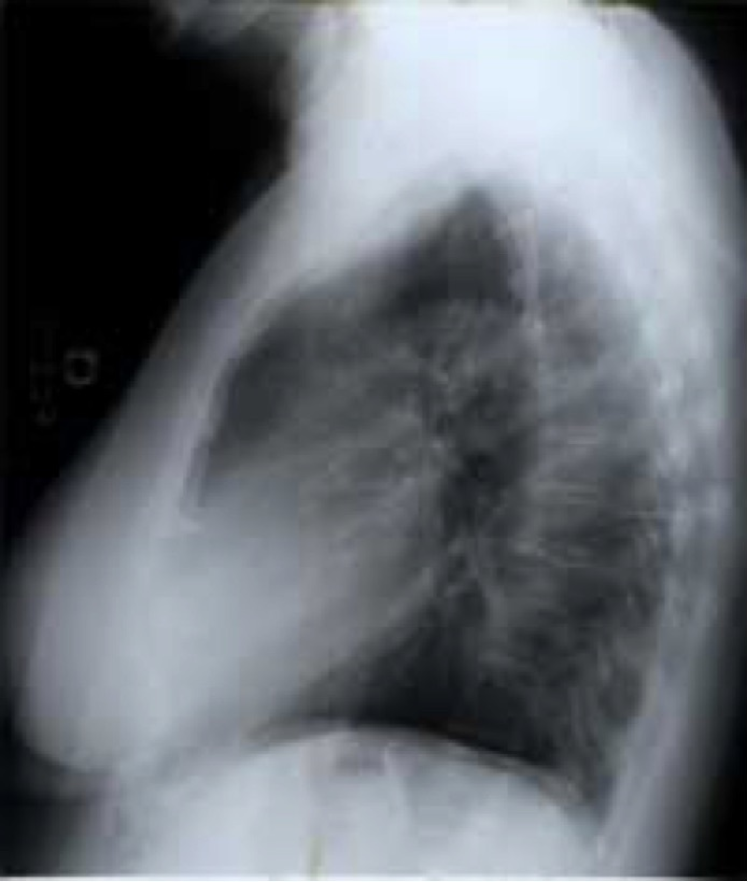

(a) P-A

Refer to caption

(b) Decubit

Figure 4: Pleural effusion in different projections: A bipedestation projection (a) shows the meniscus sign in which the fluid accumulates in the subpulmonary region, ascends through the thoracic wall and through the paramedian zone. In decubit projection (b) there is no meniscus sign. As the liquid goes to the most declining area there is a diffuse increase in hemithorax density and a loss of the net limit of the diaphragm with occupation of the pulmonary vertex by apical cap, costo-phrenic angle blunting and a thickening of the smaller fissure.

The projection information is highly relevant for diagnosis. For example, AP views, which are commonly used in pediatric patients, show an enlarged heart silhouette (Fig. 2(j)) that should not be interpreted as cardiomegaly, but merely the expected large-depth ratio of reversed organ observation (Fig. 3). Another illustrative example is the distinct pattern that pleural effusions have in the standing position (Fig. 4(a)), in which a typical meniscus sign is commonly found as opposed to decubit projections (Fig. 4(b)). Given that the number of different projections is unbalanced (for instance, PA followed by lateral projections typically comprise the majority of chest x-rays), there is the risk that none of the other projections will have sufficient instances with which to train models capable of discriminating pathological from non-pathological patterns in the context of the projection.